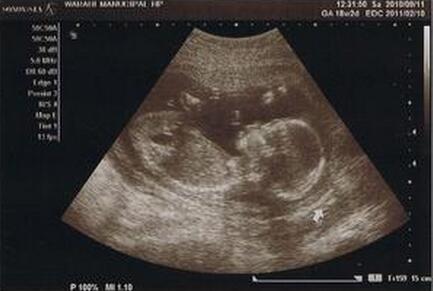

一、孕18周胎儿发育情况

你的宝宝现在从头到臀部大约长13~15厘米,重160~198克。骨骼几乎全部是类似橡胶似的软骨,以后会变得越来越硬。薄薄的皮肤下的血管清晰可见,胸脯不时地鼓起来、陷下去,这是胎儿呼吸的表现,胎儿口腔里流动的是羊水而不是空气。

怀孕18周时的胎儿在忙着伸胳膊和蹬腿呢,也就是胎动,这周胎儿的活动越来越频繁。一般18-20周就可以感觉到胎动,刚开始的胎动就像顶小水泡一样的。孕妈妈要仔细去感受哦~

2.孕16—18周你将进行第二次产检,首先你必须做基本的例行检查,包括:称体重、量血压、问诊及看宝宝的胎心音等。孕18周羊水正常值应是在3—7CM之间。平时多喝一些汤水、豆浆,有助于提升羊水质量。